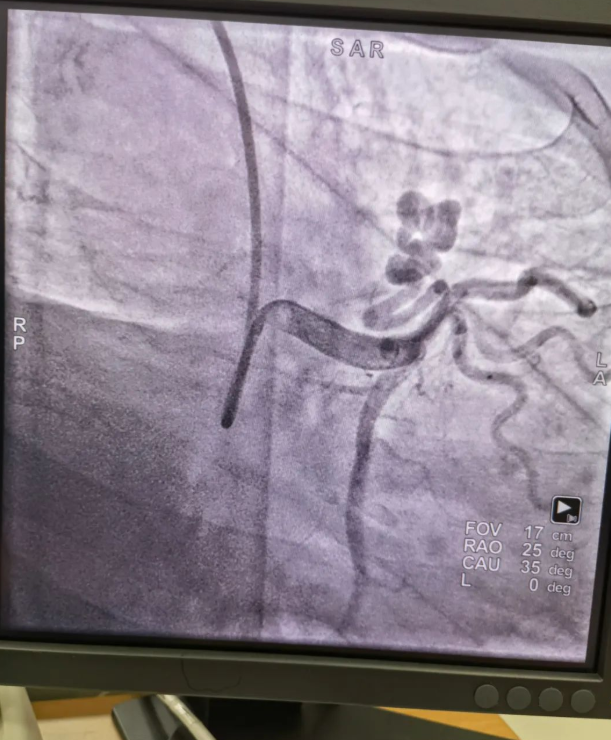

不久前,來(lái)自新疆的患者石先生去年至今反復(fù)胸悶、氣短、胸痛,就診于新疆某院,懷疑“冠心病”,住院行冠狀動(dòng)脈造影術(shù),石先生造影提示“冠狀動(dòng)脈肺動(dòng)脈瘺”,而他并非“冠心病”,所以給予的“冠心病”治療,效果不佳。出院后仍反復(fù)出現(xiàn)胸痛、胸悶、氣短等癥狀,經(jīng)親友介紹了解到西安國(guó)際醫(yī)學(xué)中心醫(yī)院心臟病醫(yī)院心臟內(nèi)科二病區(qū)曾廣偉主任,多年來(lái)潛心研究心臟病介入治療,成功主刀救治了許許多多高危復(fù)雜病例,尤其是在先心病及結(jié)構(gòu)性心臟病封堵,以及冠心病、心律失常射頻消融及起搏治療等方面積累了豐富的診療經(jīng)驗(yàn)。

此病例罕見,在曾廣偉從醫(yī)18年生涯里曾碰到有2個(gè)印象深刻的病例,患者分別是53歲和66歲,當(dāng)時(shí)建議患者入院進(jìn)行動(dòng)脈瘺的封堵術(shù),但患者和家屬考慮到這個(gè)手術(shù)案例極少,風(fēng)險(xiǎn)也高,均未接受手術(shù)治療建議,只是能采取藥物保守治療,出院后隨訪得知患者癥狀緩解效果不佳,后來(lái)在隨訪中也與53歲患者失去了聯(lián)系,而66歲患者因冠狀動(dòng)脈肺動(dòng)脈瘺出現(xiàn)反復(fù)心衰,在當(dāng)?shù)蒯t(yī)院藥物治療,短短2年時(shí)間,患者因?yàn)閯?dòng)脈瘺未及時(shí)手術(shù)失去了生命。所以此次患者石先生到訪,曾廣偉主任在詳細(xì)掌握病例資料基礎(chǔ)上,果斷建議進(jìn)行動(dòng)脈瘺的封堵術(shù)治療,為了提高手術(shù)成功率和精準(zhǔn)度,曾廣偉主任搜集相關(guān)診療資料,反復(fù)推演論證,經(jīng)過(guò)相當(dāng)充足的準(zhǔn)備工作,于5月18日成功進(jìn)行了封堵手術(shù),完全堵上了瘺口。

患者術(shù)后第2天,已經(jīng)沒(méi)有明顯的胸悶、氣短、胸痛等癥狀,目前身體狀態(tài)良好。本次手術(shù)曾廣偉主任及其團(tuán)隊(duì),采取從右手臂一根血管進(jìn)入,并在2小時(shí)之內(nèi)完美封堵,創(chuàng)口小,痛苦小。手術(shù)雖然難度大、風(fēng)險(xiǎn)高,相關(guān)案例也少,但是曾廣偉主任主刀即在巔峰,這樣一臺(tái)完美的手術(shù)靠的不是運(yùn)氣,是豐富的臨床手術(shù)經(jīng)驗(yàn),扎實(shí)的專業(yè)知識(shí)儲(chǔ)備,以及對(duì)醫(yī)療事業(yè)的孜孜追求。

冠狀動(dòng)脈瘺是指冠狀動(dòng)脈與心腔、冠狀靜脈、肺動(dòng)脈等的異常連接,是一種少見的先天性心臟病,發(fā)病率為1.3%。而冠狀動(dòng)脈肺動(dòng)脈瘺是冠狀動(dòng)脈與肺動(dòng)脈之間產(chǎn)生的一種血管性瘺口,導(dǎo)致冠狀動(dòng)脈里的血液流入肺動(dòng)脈里,使冠狀動(dòng)脈里血液流量減少,出現(xiàn)心肌供血不足,冠狀動(dòng)脈肺動(dòng)脈瘺會(huì)使患者出現(xiàn)胸部疼痛、胸悶、呼吸困難、頭暈、乏力等一系列癥狀,隨著疾病不斷進(jìn)展,可引發(fā)心功能的障礙和心肌缺血,肺動(dòng)脈會(huì)逐漸形成肺動(dòng)脈高壓,還可能導(dǎo)致動(dòng)脈瘤的破裂,甚至威脅病人的生命安全,所以早期發(fā)現(xiàn)和治療冠狀動(dòng)脈肺動(dòng)脈瘺,對(duì)病人的預(yù)后改善具有重要的意義。